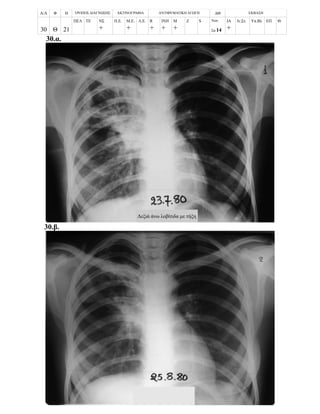

Περίπτωση 23η:

Α/Α Φ Η ΤΡΟΠΟΣ ΔΙΑΓΝΩΣΗΣ ΑΚΤΙΝΟΓΡΑΦΙΑ ΑΝΤΙΦΥΜΑΤΙΚΗ ΑΓΩΓΗ ΔΘ ΕΚΒΑΣΗ

23 Α 14

ΠΕΛ ΤΕ ΝΣ

+

+ ++

+++ R

ΙΝΗ

Μ

Z S Νοσ.

Σπ.14

ΙΑ

Ιν.Στ. Υπ.Βλ ΕΠ Θ.

23.α. Επαφή

23.β.